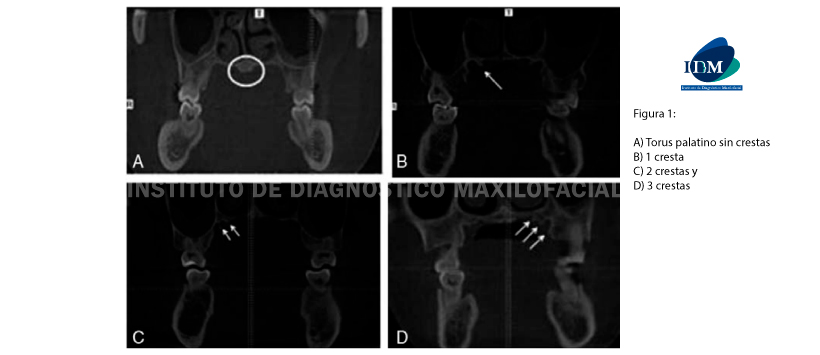

Es por ello que el objetivo de este estudio es evaluar las características morfológicas de la región palatina posterior entre la población china (más específicamente, los surcos palatinos mayores, las crestas, los puentes y las estructuras de los torus palatinos) y hacer comparaciones entre diferentes grupos étnicos y minorías. (Figura 1)

Para lo cual se recolectó un total de 323 tomografías computarizadas de haz cónico para analizar la presencia de surcos, crestas, puentes o torus palatino. Los datos fueron recolectados mediante el reconocimiento de las ranuras, crestas, puentes y torus palatino; calculando el número de esas estructuras anatómicas.

Obteniendo como resultado tres manifestaciones morfológicas diferentes del surco palatino mayor (GPG) que se encuentran en las regiones molares superiores 1º y 2º son las siguientes: sin surco, 1 surco y 2 surcos. El número de crestas varió de 0 a 3. Y la incidencia de torus palatinas fue del 29%. Además, se encontró una correlación positiva entre la presencia de crestas / GPG y la edad en la región del segundo molar.